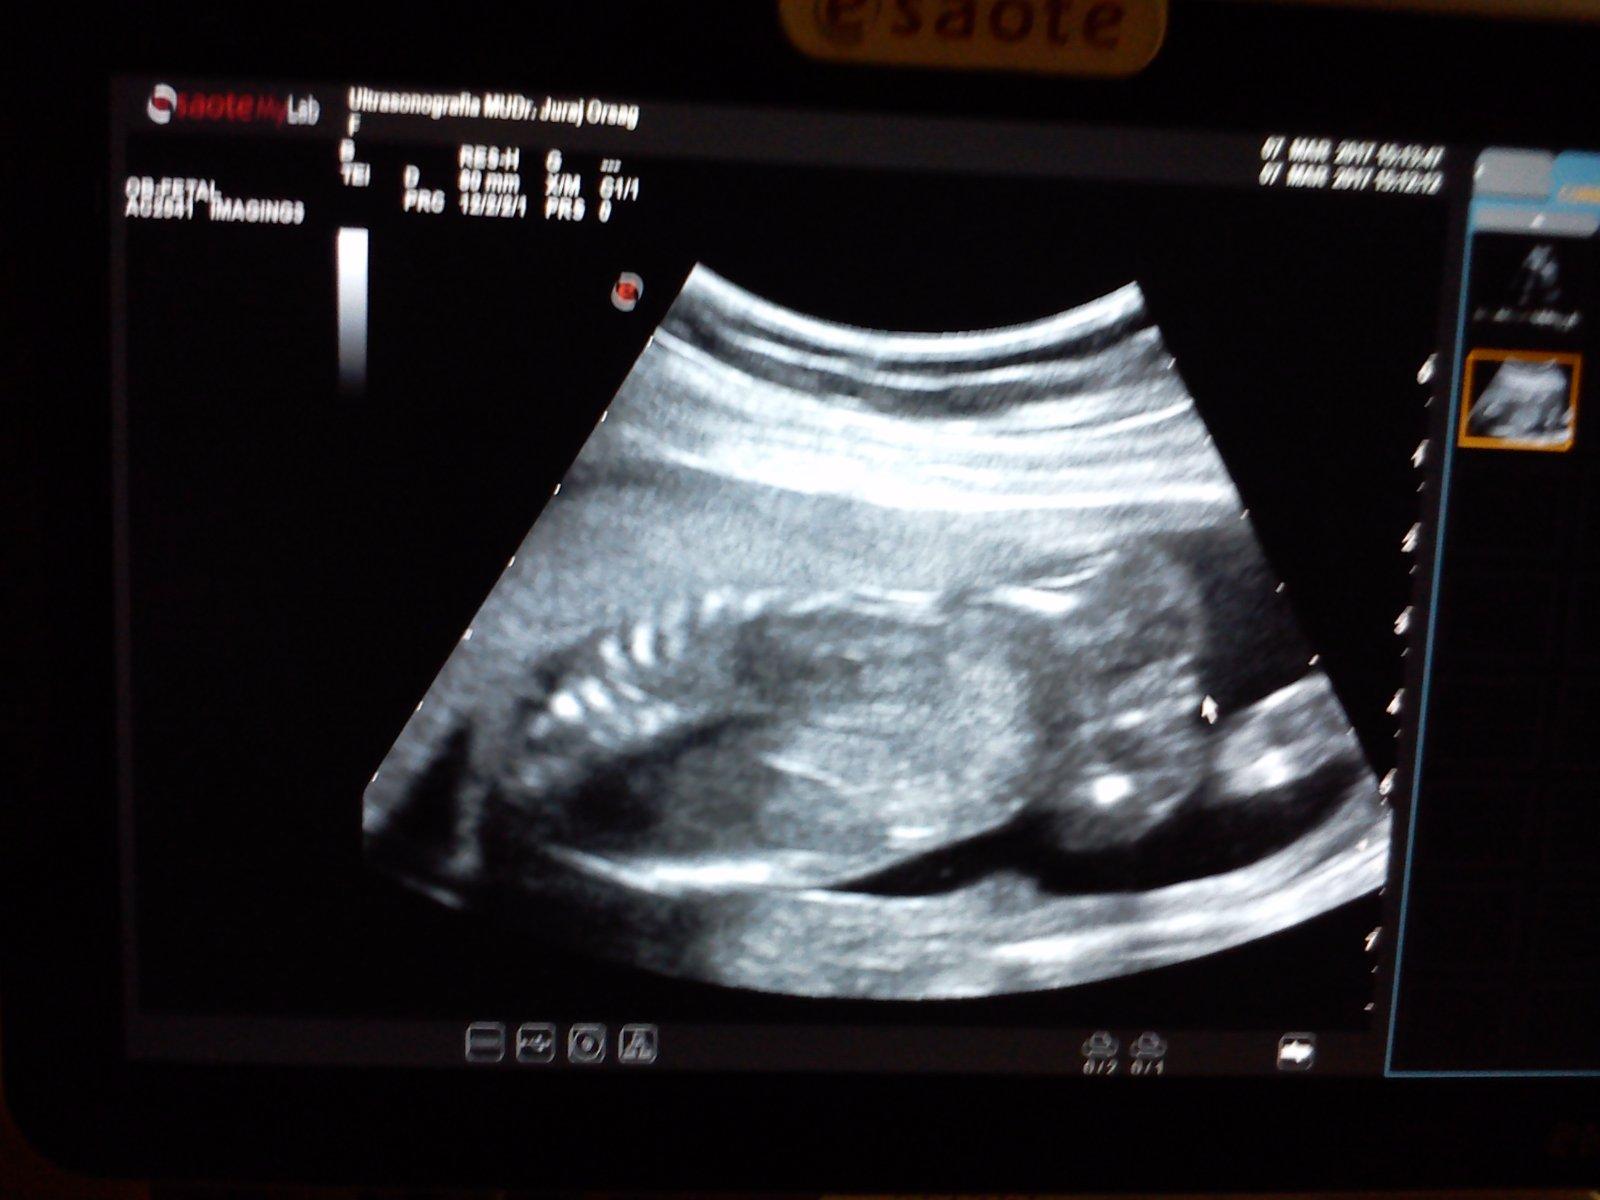

7.3.2017 mame cca 25 cm a 380 g a vidime kavove zrno :D dnes sa stala z Lukasa nasa Janka, no uz jej ostava Luna ❤